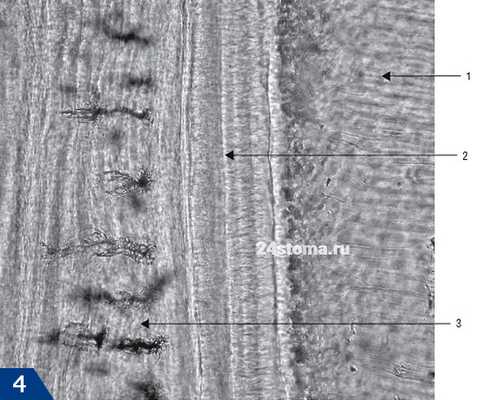

Гистологический препарат (пульпа зуба и околопульпарный дентин) -

Где 1 - это дентин (где 1а - калькосфериты, 1б - предентин).

Где 2 - пульпа зуба (где 2а - периферический слой, состоящий из одонтобластов, 2б - зона, бедная клетками, в промежуточном слое пульпы, 2в - зона, богатая клетками, в промежуточном слое пульпы, 2г - центральный слой пульпы).